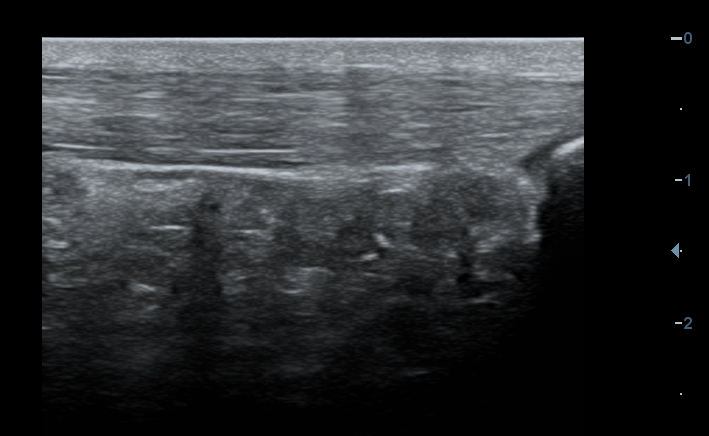

Obr. 1: Patologicky rozšířená Achillova šlacha (pruh s vláknitou strukturou v horní polovině snímku) s mírnou poruchou integrity vláken